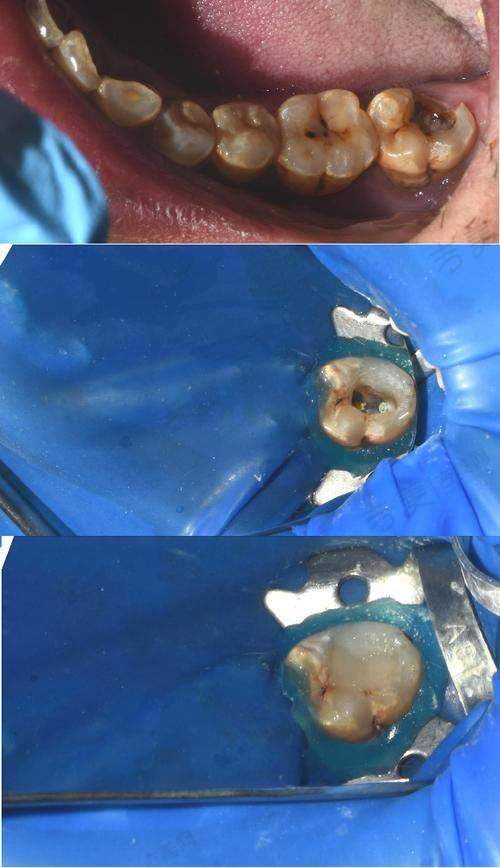

烟台德韩万达院口腔门诊部拥有众多特色项目。即刻种植牙是其一大亮点,该技术能够在拔牙后立即植入种植体,大大缩短了治疗周期,减少了患者的痛苦。美国3种种植体和瑞士ITI种植体,为患者提供了更多的选择,这些种植体具有良好的生物相容性和稳定性,能够确保种植成效。氟斑牙治疗采用精良的技术和方法,有效改善牙齿外观和色泽。儿童龋齿治疗针对儿童牙齿特点,采用温和、微痛的治疗方式,让孩子轻松摆脱龋齿困扰。地包天矫正项目,医生会根据患者的具体情况制定个性化的矫正方案,帮助患者修复正常的咬合关系。洗牙项目采用精良的设备和技术,能够有效清除牙齿表面的污垢和菌斑,预防口腔疾病。口腔预防保健则注重从源头预防口腔问题,为患者提供专精的口腔卫生指导和建议。拔牙、牙套、活动义齿、牙齿美白等项目也都有着专精的医生团队和精良的技术设备支持,能够为患者提供优质的诊疗服务,充分体现了烟台德韩万达院口腔门诊部的实力。